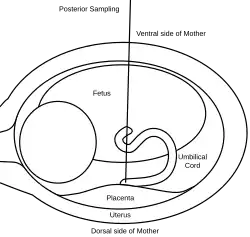

A 20 or 22 gauge spinal needle is typically used in PUBS and may be prepared with an anticoagulant, which helps to reduce the risk of clot formation.[11] During the procedure, the first step is to locate a relatively stable segment of the umbilical cord. A typical sampling site would be where the segment of the umbilical cord is closest to the placenta. However, there is a risk of maternal blood contamination at this site. Blood sampling may be achieved with more ease if the placenta is in the anterior position. However, if the placenta is in the posterior position, the fetus might block direct access to the umbilical cord. Once the umbilical cord is reached and the correct position of the needle is confirmed, the fetal blood is drawn. The needle is removed after all necessary samples are taken. The site of puncture is monitored after the procedure for bleeding. Also, if the fetus is viable, fetal heart rate is monitored post-procedure for one to two hours.[9]